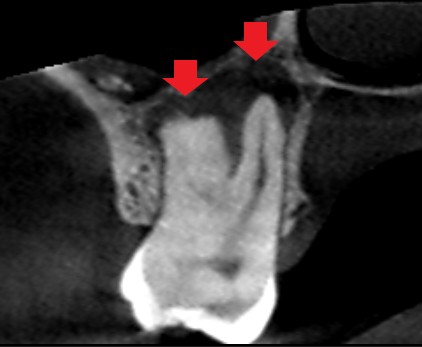

初診時の矢状断のCT画像です。

赤い矢印の先に黒い膿の影がみられ、膿は大きく埋伏している第三大臼歯(親知らず)に達しています。